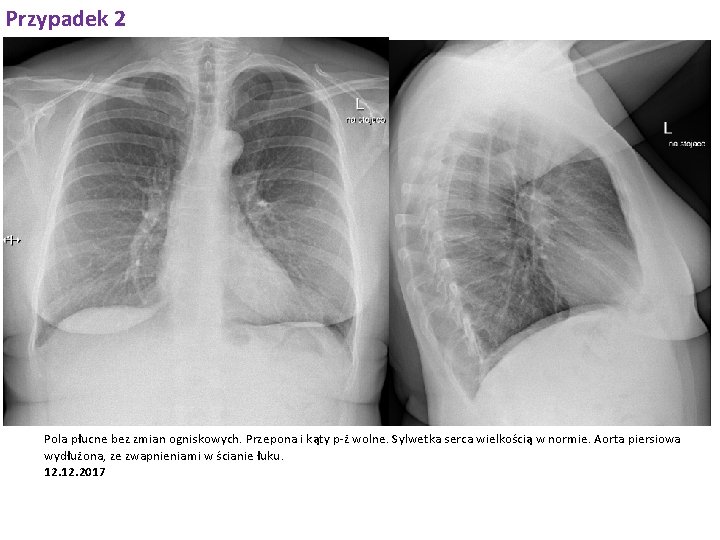

Przypadek 2 Pola płucne bez zmian ogniskowych. Przepona i kąty p-ż wolne. Sylwetka serca wielkością w normie. Aorta piersiowa wydłużona, ze zwapnieniami w ścianie łuku. 12. 2017